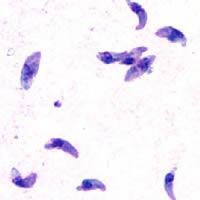

TIL nearly one in three humans have the parasite toxoplasma gondii. Passed from cats, and only capable of reproducing in cats, it potentially has a higher rate of schizophrenia and suicidal ideation.